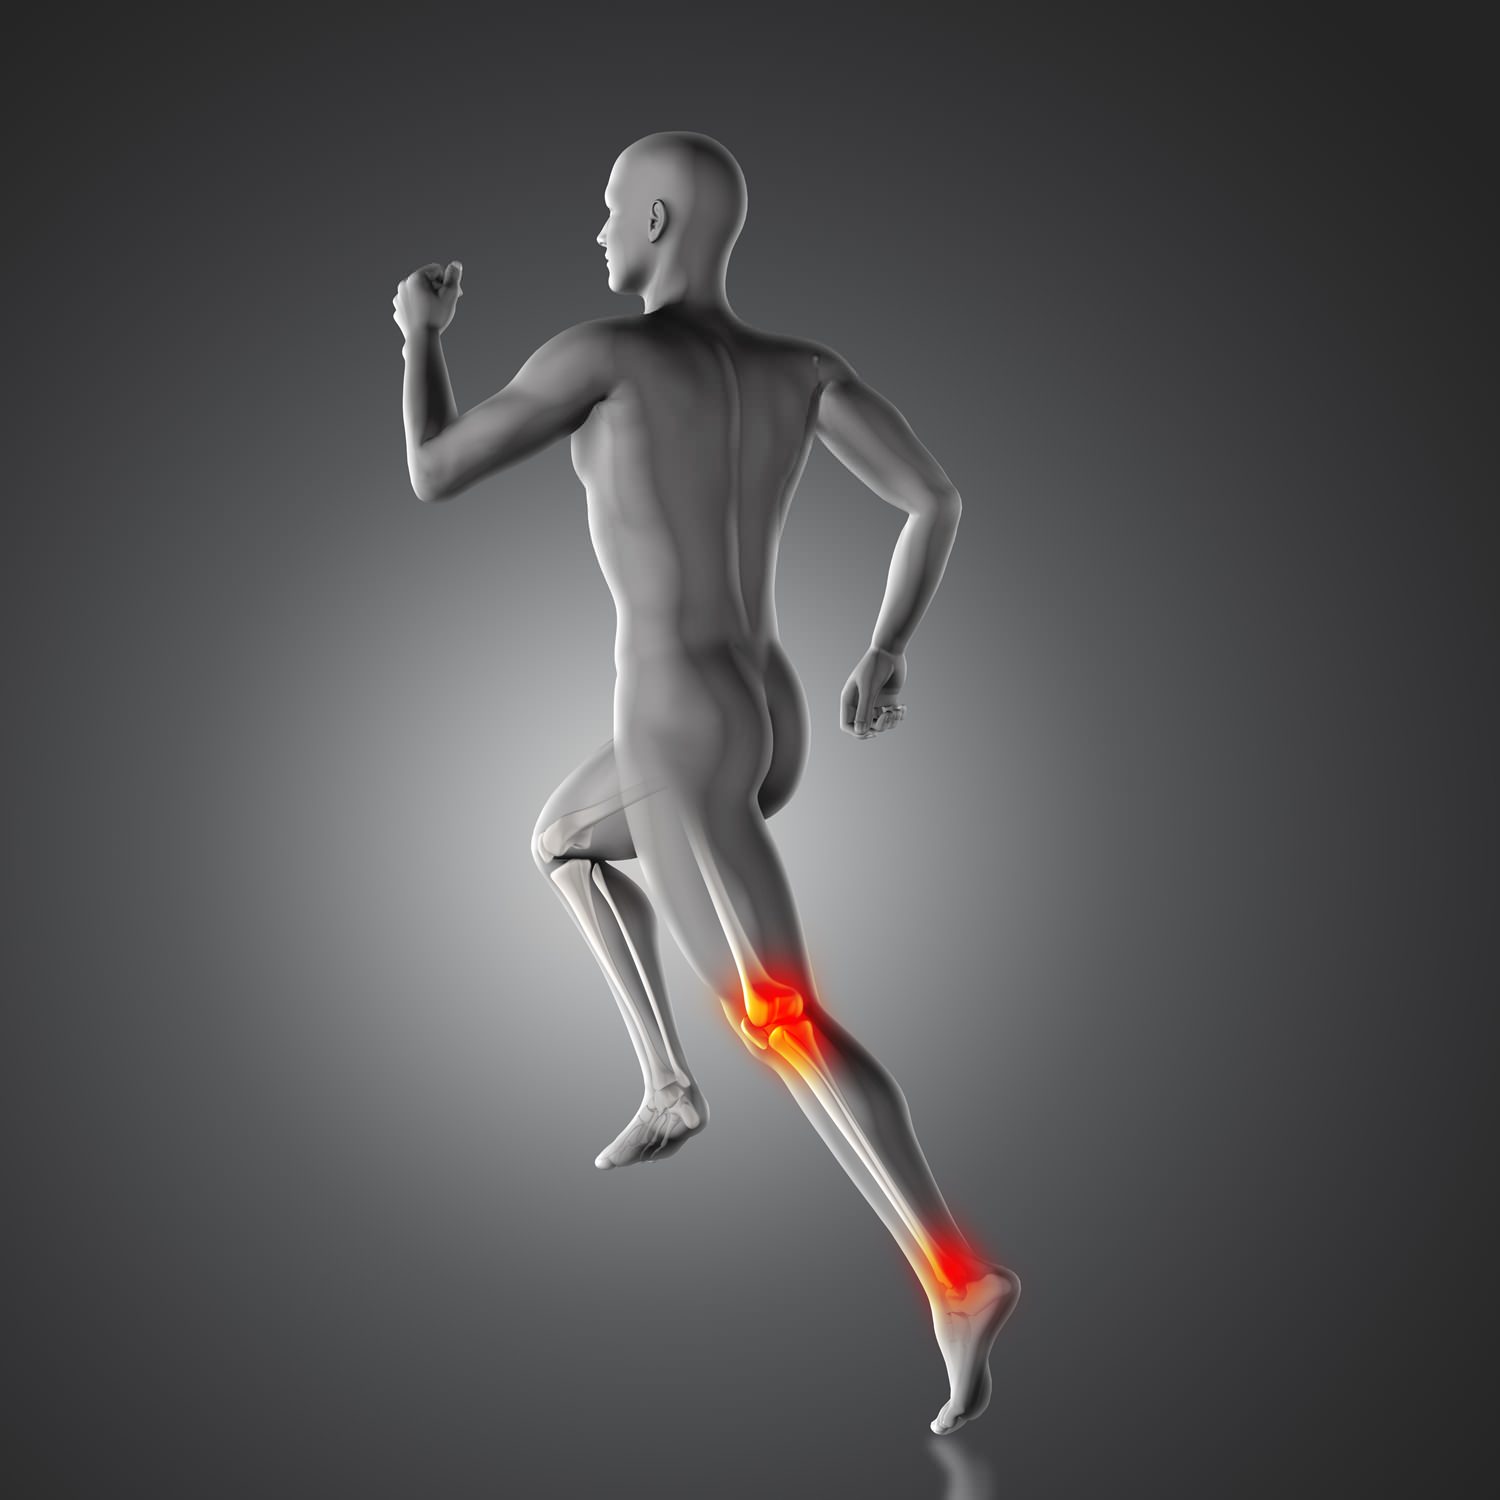

Spor ve fiziksel aktiviteler, sağlıklı bir yaşamın vazgeçilmez parçalarıdır. Ancak yoğun antrenmanlar, ani hareketler ve kazalar sonucu oluşan yaralanmalar, yaşam kalitesini düşürebilir ve hareket kabiliyetini kısıtlayabilir. Sümer Ortopedi olarak, spor yaralanmalarının tedavisinde uzmanlaşmış ekibimizle, hareket özgürlüğünüzü ve performansınızı yeniden kazanmanıza yardımcı oluyoruz. Artroskopi ve spor yaralanmaları cerrahisi alanındaki deneyimimizle, en güncel ve etkili tedavi yöntemlerini sunuyoruz.

Spor yaralanmaları, kaslar, bağlar, tendonlar ve kemikleri etkileyen çeşitli hasarları içerir. Bu yaralanmalar, sporcunun performansını ve yaşam kalitesini olumsuz etkileyebilir. Sümer Ortopedi olarak, spor yaralanmalarının tedavisinde multidisipliner bir yaklaşım benimsiyoruz.